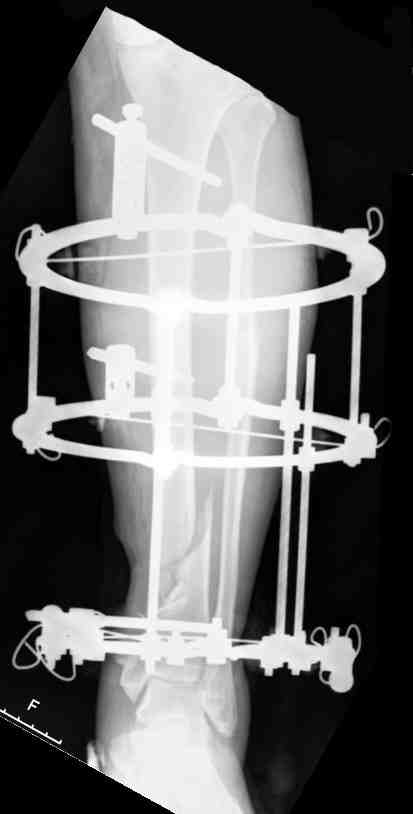

Операционные снимки перед и после наложения аппарата Илизарова

In operation room before and after Ilizarov apparatus has been applied

Послеоперационные рентгенограммы

Postoperative X-rays